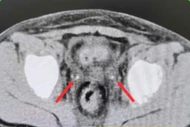

Bệnh viện Việt - Hàn Đà Nẵng đã bóc tách thành công khối u nang buồng trứng kích thước lớn, bảo vệ chức năng sinh sản cho bệnh nhân.

Sau nhiều giờ nghẹt thở, bằng sự kết hợp nhuần nhuyễn giữa nội soi thăm dò và mổ mở, khối u lớn đã được lấy ra trọn vẹn, buồng trứng được bảo vệ thành công.